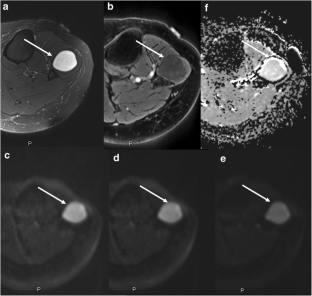

Fig. 2